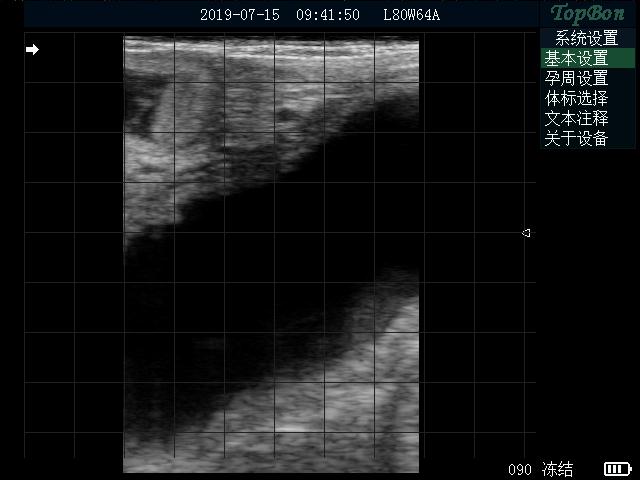

首先要給牛固定,最好有限位欄,防止被牛踩到。接下來給牛掏糞,因為牛的糞便會影響B(tài)超使用效果。第三步,手持B超探頭從牛的肛門伸入體內(nèi),伸入距離大概到手的肘部位置,用手按壓探頭,使B超聲窗和直腸緊密接觸,然后聲窗左右來回擺動,觀察到牛的子宮或者胎仔停止擺動,仔細(xì)觀察效果。不同時期胎仔的成像效果不同,這要結(jié)合牛的配種時間和臨床經(jīng)驗來判斷是否懷孕,下面是母牛懷孕3個月左右效果。拓邦B超不僅能清晰檢查懷孕情況,還能通過軟件測量,測量胎仔大概懷孕天數(shù)和預(yù)產(chǎn)日期,便于初學(xué)者學(xué)習(xí)使用。